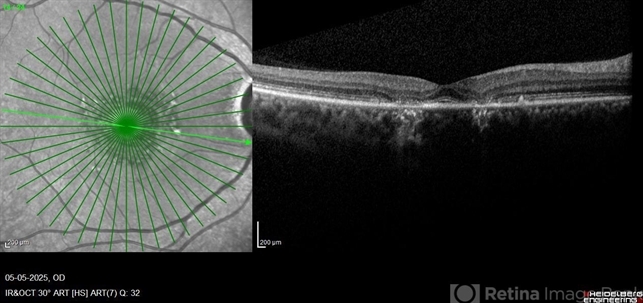

- Benign concentric annular macular dystrophy

- OCT image